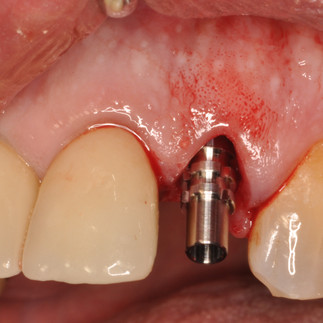

2.2 CERVICAL ROOT FRACTURE ,GENTLE EXTRACTION ,IMPLANT INSERTION PARALLEL TO THE PALATINE WALL,PROSTHETIC FIT,NO OCCLUSAL LOAD.

PROSTHETIC CONTROL FOUR YEARS